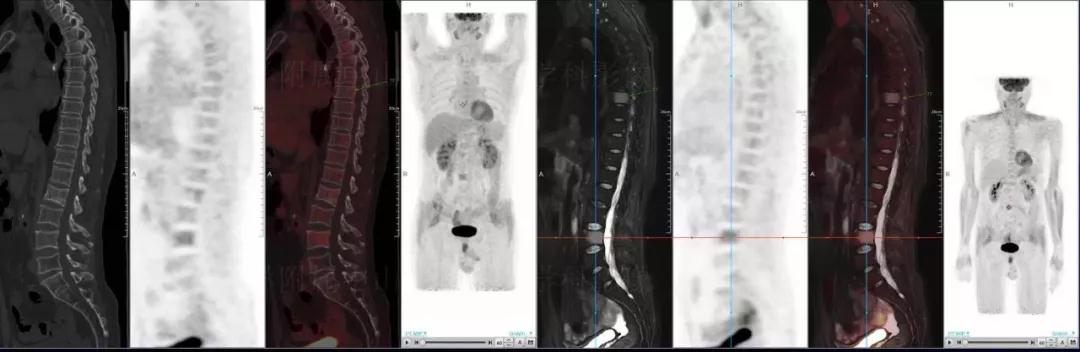

多發(fā)性骨髓瘤

中山醫(yī)院核醫(yī)學科基于聯(lián)影“時空一體”超清TOF PET/MR的融合顯像優(yōu)勢,進行了大量的臨床掃描,發(fā)現(xiàn)多例由MGUS向多發(fā)性骨髓瘤轉(zhuǎn)變,并從中總結(jié)出了一定的共同征象,未來可能實現(xiàn)多發(fā)性骨髓瘤的早期篩查。此外,PET/MR在多發(fā)性骨髓瘤的療效評估方面,也存在顯著優(yōu)勢。

(男性,53歲。確診多發(fā)性骨髓瘤10月。經(jīng)過7周期VCD方案化療后,現(xiàn)行療效評價。)